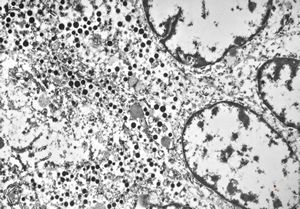

F, 68y. | APUD carcinoma mammae

F, 68y. | APUD carcinoma mammae - Bodian impregnation